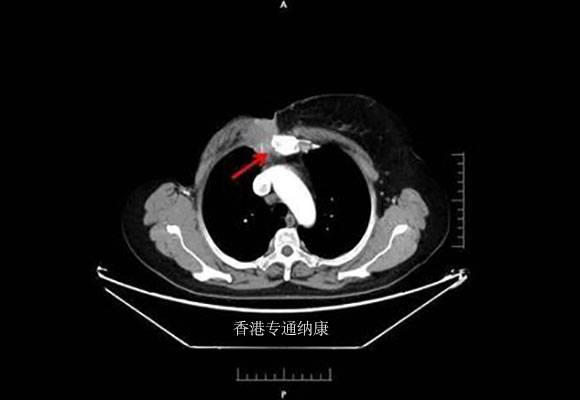

了解了HER2的检测和表达情况,接下来要介绍的这款抗癌药物DS-8201a,是一种新型的靶向HER2的单克隆抗体偶联药物,有报道DS-8201a治疗低表达HER2的乳腺癌有一定疗效。下面癌度分享一个案例让大家了解DS-8201a的神奇之处。